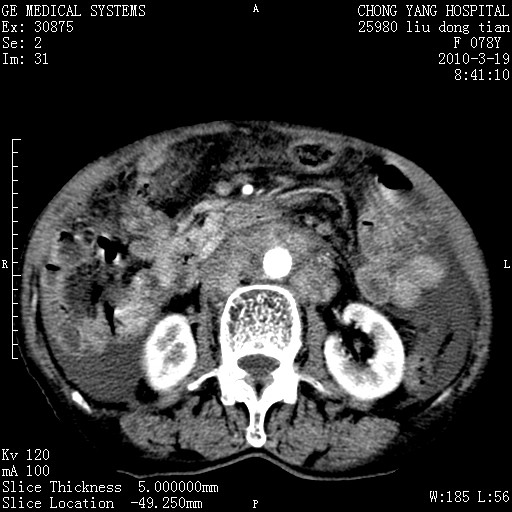

标题: CT25199:F 78Y 腹胀半年 消瘦乏力 [打印本页]

胆囊壁增厚并明显强化,胆囊癌伴多发转移瘤可能性大,淋巴瘤不除外,右肾囊肿,胸腹水.

考虑nhl,肝、脾、腹膜腔及腹膜后多发淋巴结受侵,腹水,右肾囊肿,慢性胆囊炎,右侧少量胸腔积液。

胰头有肿块形成,胰头ca伴肝脾、腹膜腹膜后转移

胆囊有软组织影有强化,支持胆囊癌,肝脾、腹膜后淋巴结转移。

nhl的淋巴结多围绕主动脉,而且主动脉会移位,所以不考虑nhl。

分开来讲:肝左叶、尾叶病灶有不均强化像肝癌;

脾脏病灶无强化,像多发囊肿或淋巴管瘤,不除外淋巴瘤(低强化);

胆囊增生性病变:胆囊癌,腺肌增生症,慢性胆囊炎;

肝门、胰腺头、腹膜后多个团块: 淋巴瘤,转移;

腔静脉肝内段细小有无布加可能?

一元论最好了 淋巴瘤所致改变; 胆囊癌转移不像,胆囊周围肝组织清晰,肝癌淋巴结转移?三元论都不止。

胰头ca伴肝脾、腹膜腹膜后转移!

最后报的胰头癌多发转移,脾脏单独考虑囊肿或淋巴管瘤。